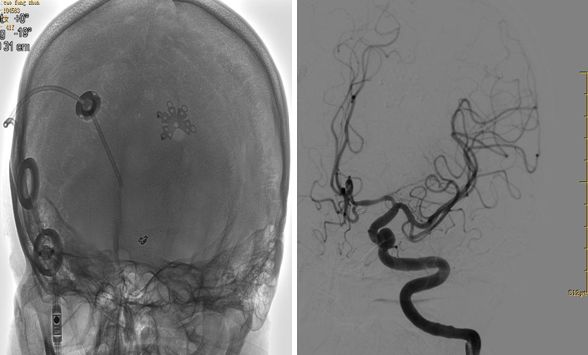

2018年5月4日:入院复查造影,见瘤颈复发,第二次行动脉瘤栓塞术

2018年5月4日,第二次支架辅助下栓塞

三个月后复查,未见复发,患者恢复良好

疑惑:第一次栓塞后,再次复查弹簧圈散开,原因?假性动脉瘤?

最终结果:复查造影动脉瘤未见复发,弹簧圈又回缩成一团。患者恢复良好。